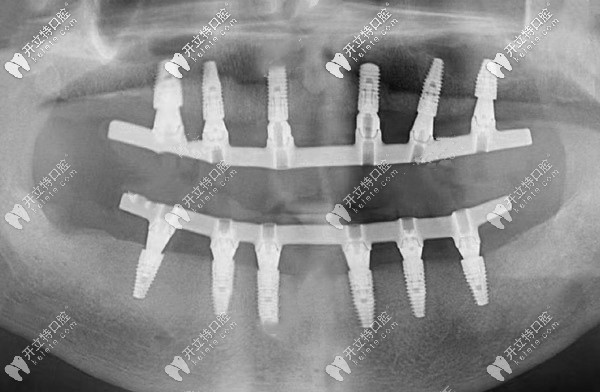

all-on-six即刻種植牙的全景片

(這就是all-on-six即刻種植后的全景片)